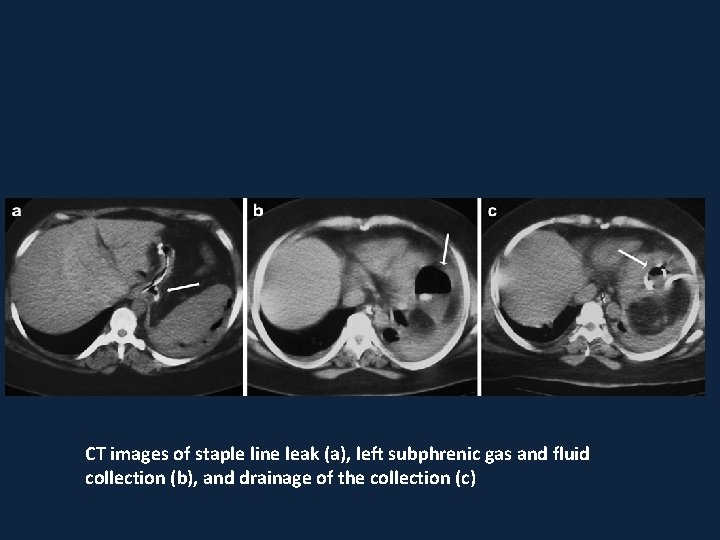

CT images of staple line leak (a), left subphrenic gas and fluid collection (b), and drainage of the collection (c)

• postoperative air-fluid collection adjacent to GE junction consistent with staple line leak

• In all patients, a UGI was routinely performed on POD 3 to exclude complications, primarily staple line leaks and strictures, and begin gradual fluid intake. • If a leak was detected, further imaging investigation by CT was performed to confirm the finding and exclude abscess formation.